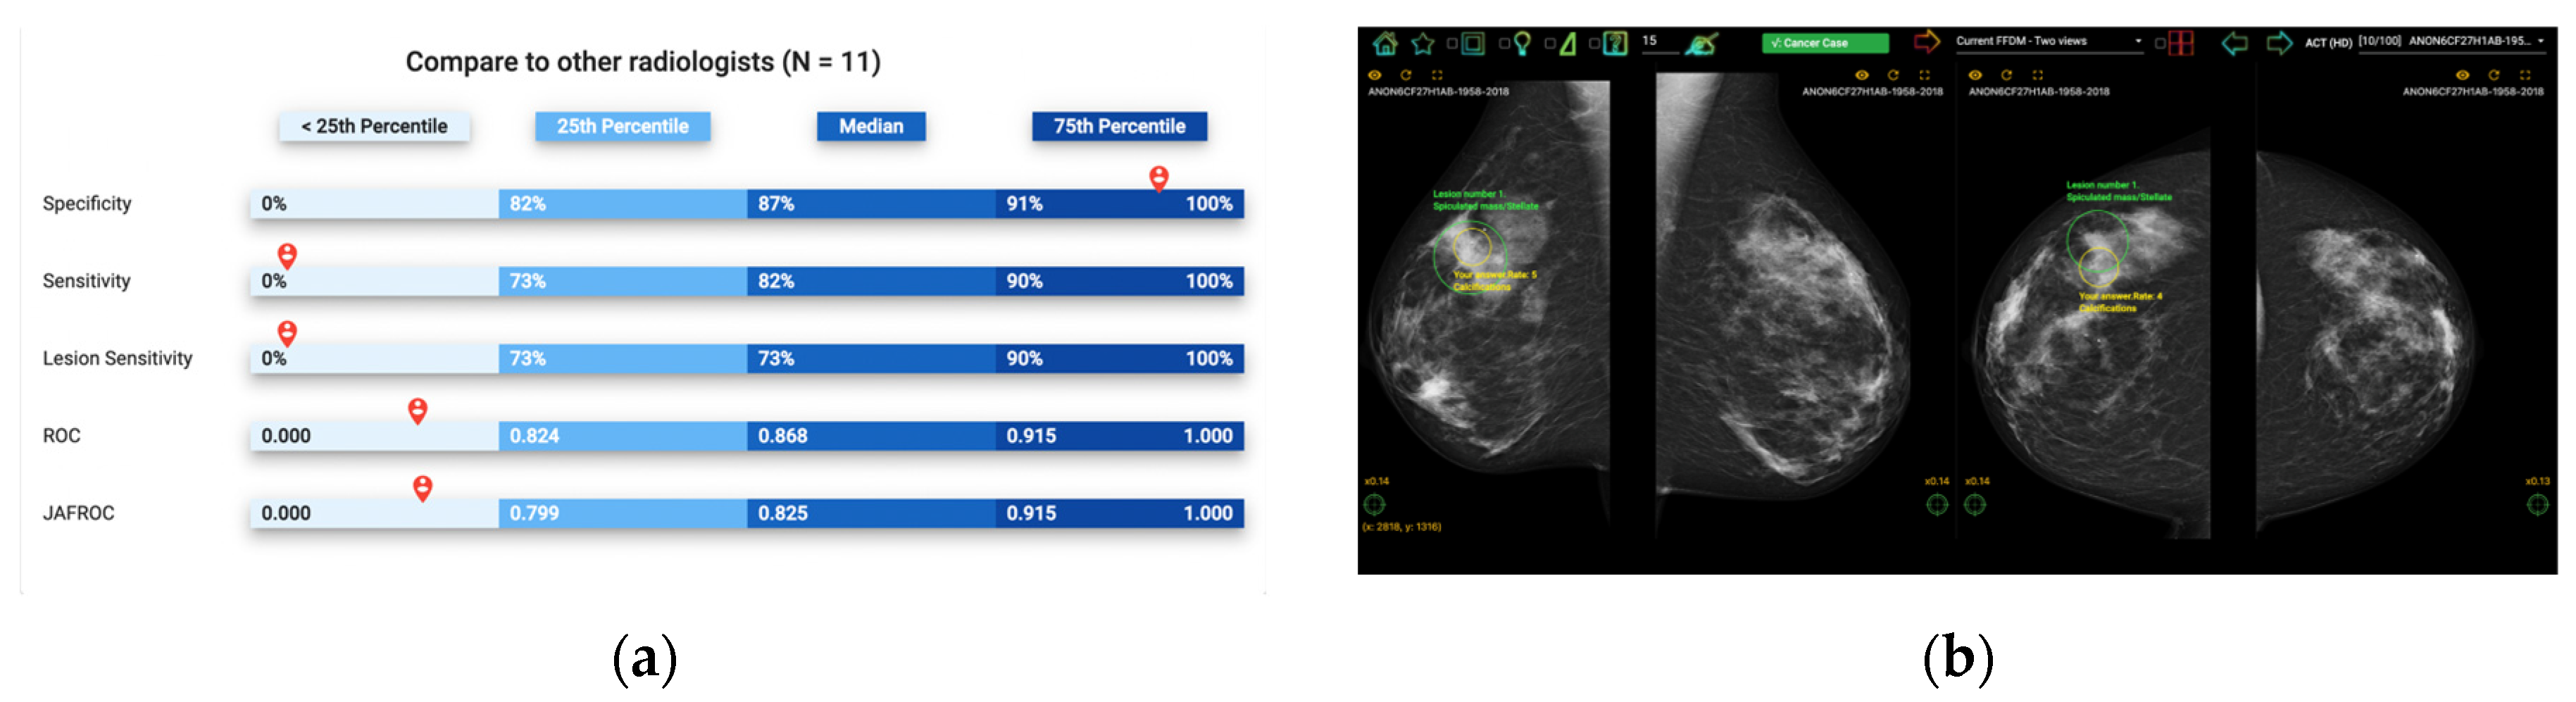

Figure 1.

Illustration of Breastscreen REader Assessment STrategy (BREAST) platform for reading mammographic images. (a) Once readers completed the assessment, they were ranked against their peers anonymously. (b) A visual display of all errors and the truth.